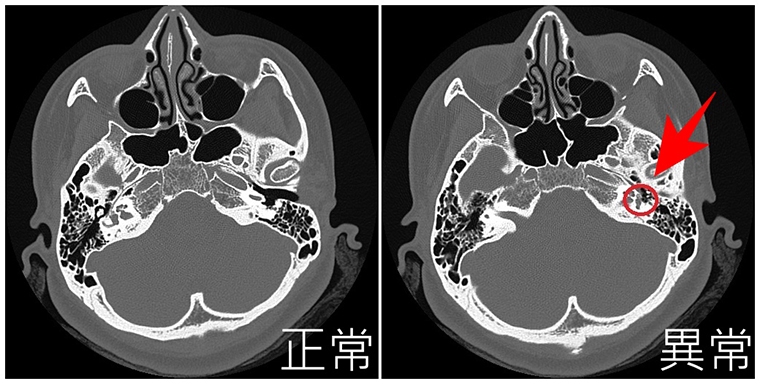

亞洲大學附屬醫院耳鼻喉科主治醫師陳厚匡指出,患者到院後,先詢問其病史、聽力下降時間及相關家族史,並安排理學檢查與聽力檢查,確認是「傳導性聽力損失」而非「感音神經性聽力損失」,之後藉由CT斷層掃描,排除可能病因如中耳炎或中耳腫瘤後,果然在鐙骨底板發現中耳骨質病變,確認是耳硬化症(Otosclerosis)惹禍。

關於耳硬化症典型特徵,陳厚匡說明,主要是鐙骨周圍緻密骨頭結構改變,病變骨頭被吸收後,由海綿狀血管性骨骼取代,最後形成硬化骨質取代海綿狀骨骼,此異常骨骼生長可能會導致鐙骨底板發生機械性固定,並破壞聽骨鏈傳遞聲音,使得聲音無法有效傳遞至內耳,從而造成傳導性聽力損失。